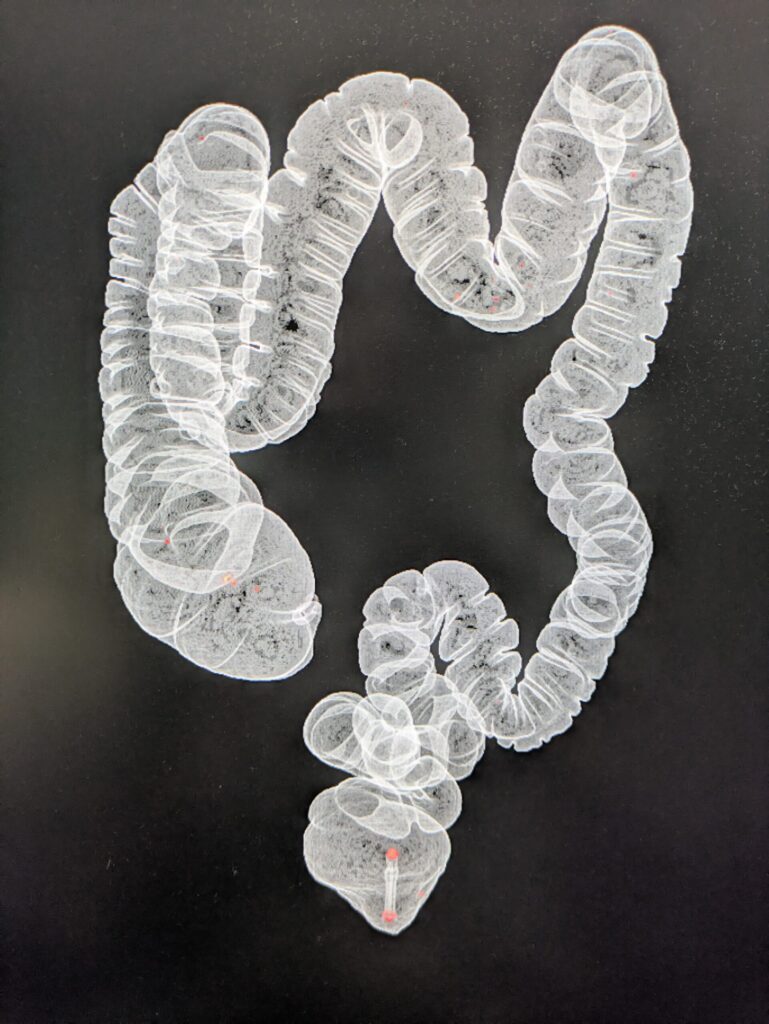

CTC uses CT scanning to create 3D images of the colon, allowing doctors to “virtually” inspect the inside without inserting a scope.

4. 3D images and maps are generated with software.